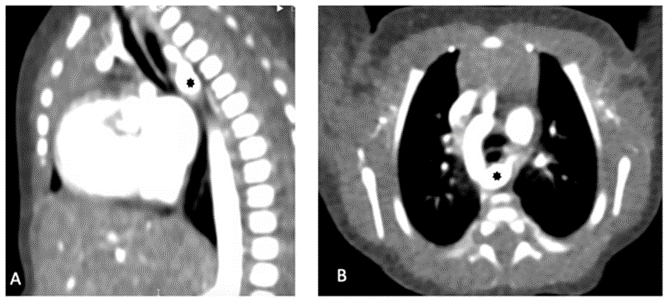

The mother was admitted to the ICU and placed on sotalol. We noted the termination of fetal tachyarrhythmia after treatment. No maternal risk factors were identified. The infant, after birth, remained stable with a heart rate of 130-145 beats per minute and had a normal sinus rhythm on an electrocardiogram (ECG). An echocardiogram showed moderate to large patent ductus arteriosus with bidirectional shunting, torturous aortic arch with normal left and right ventricular function. A cardiac computed tomography angiography confirmed a right-sided aortic arch with Kommerell diverticulum and aberrant left subclavian artery (Figure 2, panels A and B).

Figure 2: Panel A: Cardiac computed tomography angiography (Sagittal view), showing aberrant left subclavian artery with prominent common Kommerell diverticulum (black asterisk) compressing the esophagus posteriorly.

Panel B: Cardiac computed tomography angiography (Axial view), showing right-sided aortic arch with aberrant left subclavian artery with prominent common Kommerell diverticulum (black asterisk) compressing the esophagus posteriorly.